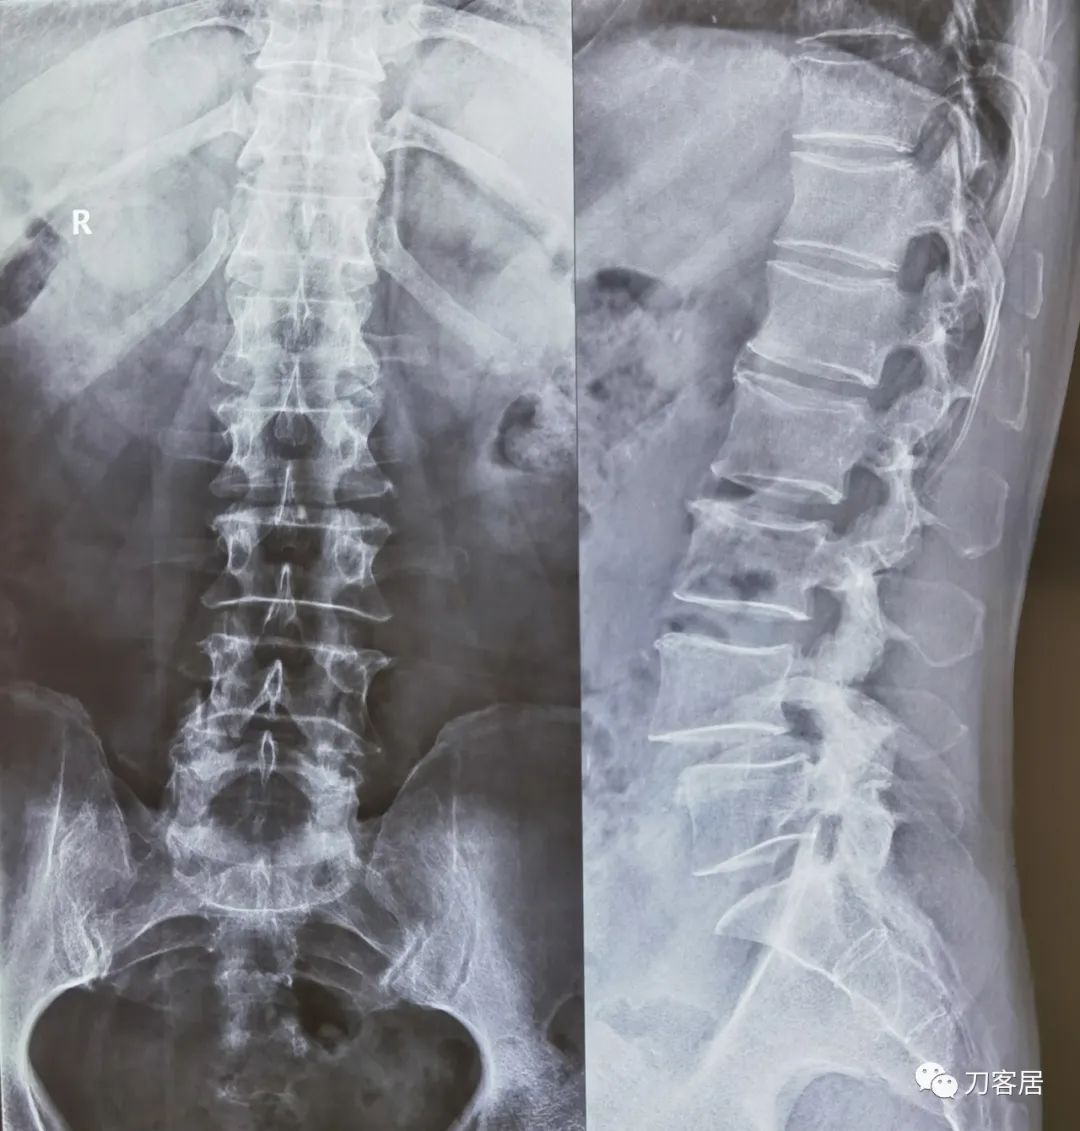

患者自带腰椎MRI提示腰4椎体前滑脱1度,腰4-5椎间盘突出,椎管狭窄。

给予腰椎6位片检查,以了解腰椎的稳定性及是否存在峡部裂,腰椎6位片提示右侧腰4峡部裂,腰4椎体稳定性差。

图1. 20220615腰椎正侧位X线片